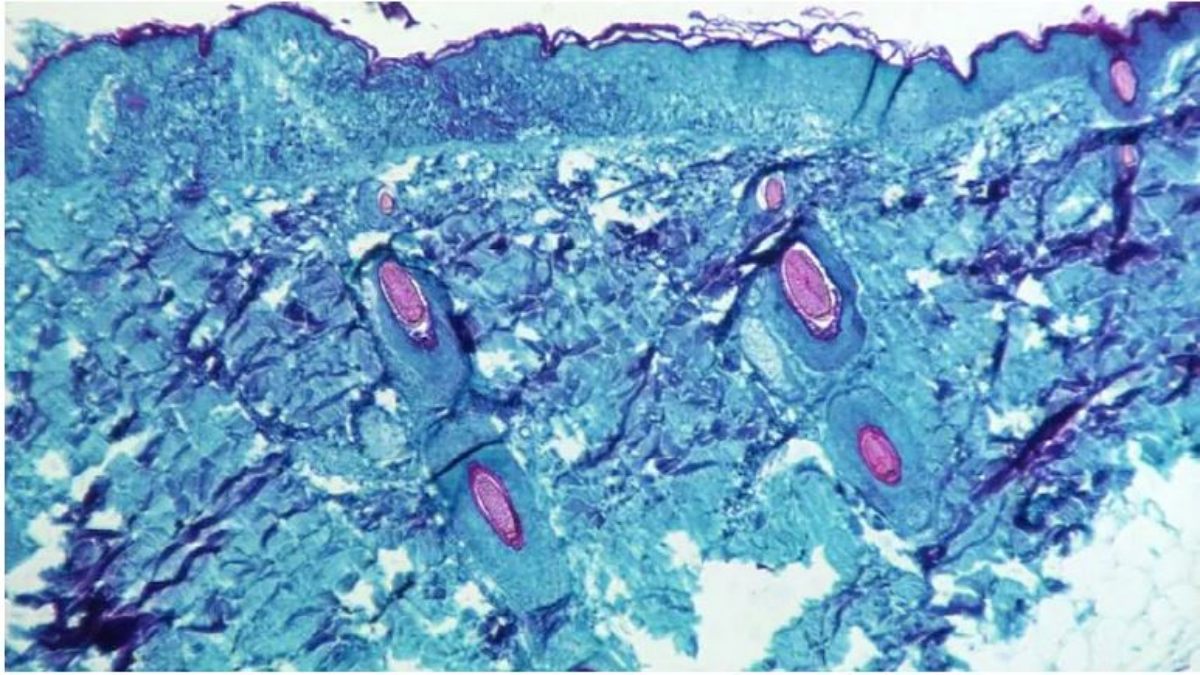

Within a week or two, the infected individual develops rashes which further lead to pustules. The disease lasts for 2 to 4 weeks.